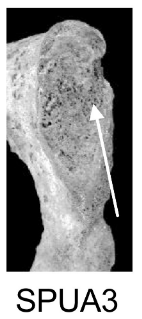

Demi-face postérieure (SPUA)

Changements morphologiques de la demi-face postérieure de la symphyse pubienne, incluant la présence et l'orientation de crêtes et sillons, et le processus de remodelage osseux.